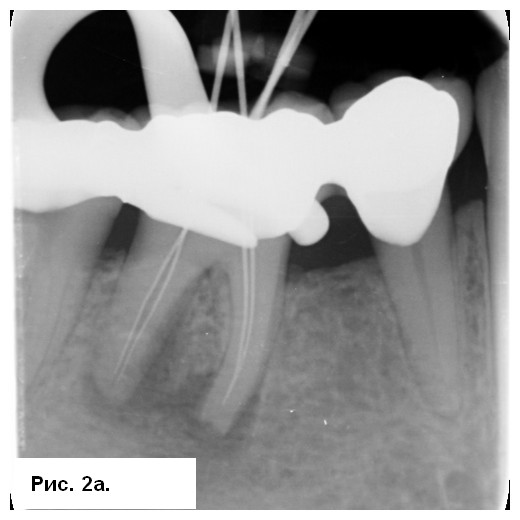

На рентгенограмме (рис. 1а) отмечались большие радиолюсцентые очаги на обоих корнях. Был поставлен диагноз: «некроз пульпы и острый апикальный абсцесс зуба 46». После консультации со стоматологом-ортопедом было принято решение провести эндодонтическое лечение с доступом к корневым каналам через существующую коронку. После вскрытия полости зуба было получено большое количество гнойного отделяемого с кровью (рис. 1b). Дренажу благоприятствовала ирригация 3 % NaOCl (рис. 1с), проведена инструментация корневых каналов системой 2Shape (MICRO-MEGA) и определена рабочая длина (рис. 2.а). Корневые каналы были заполнены гидроксидом кальция.

Симптоматика исчезла в последующие несколько дней. Второе посещение было проведено через 3 нед. Со слов пациента, зуб был асимптоматичным. После изоляции корневые каналы были вскрыты, проведена эвакуация гидроксида кальция. Затем каналы обтурировали биокерамическим силером BioRoot RCS (Septodont) методом одного штифта (рис. 2b) и выполнено композитное восстановление (рис. 2с). Была сделана послеоперационная радиография (рис. 3а), пациент записан на регулярные осмотры.